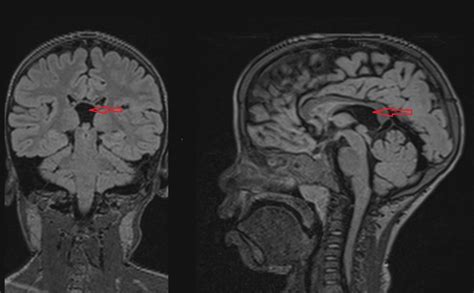

Diagnosing abnormalities in the Cavum Veli Interpositi typically involves the use of advanced imaging techniques. Magnetic Resonance Imaging (MRI) is the most commonly used method for visualizing the Cavum Veli Interpositi and other structures within the brain. MRI provides high-resolution images that allow clinicians to assess the size, shape, and position of the Cavum Veli Interpositi, as well as any potential abnormalities.

Another clinical example involves a patient with schizophrenia who was found to have an enlarged Cavum Veli Interpositi on MRI. The patient's symptoms, including hallucinations and delusions, were correlated with the structural abnormalities in the Cavum Veli Interpositi, providing further evidence of its involvement in psychiatric disorders.

• cavum veli interpositi mri